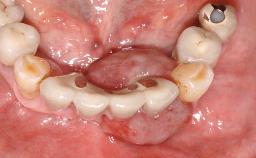

Management of a Fractured Implant Supporting a Screw-retained Metal-ceramic Restoration

The fracture of an implant after it has been restored is one of the most severe complications. It most frequently occurs in partially edentulous jaws (1.5%). Most implant fractures involve implants with a diameter of 3.75 mm made of commercially pure titanium (Eckert 2010). Unfortunately, many cases are not reported or documented by the clinicians involved in resolving the problems created by the fracture. This case report describes the management of an implant fracture at site 36 in a middle-aged male patient. The implant had been restored with a screw-retained metal-ceramic crown.